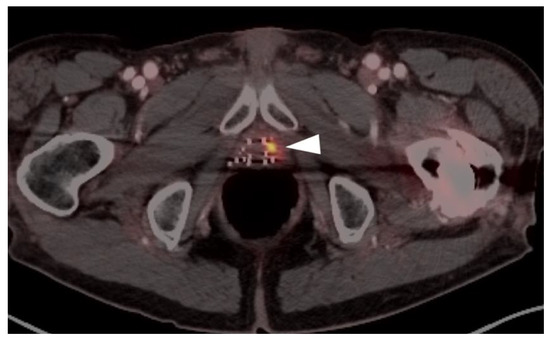

- Scher, B.; Seitz, M.; Reiser, M.; Hungerhuber, E.; Hahn, K.; Tiling, R.; Herzog, P.; Reiser, M.; Schneede, P.; Dresel, S. 18F-FDG PET/CT for staging of penile cancer. J. Nucl. Med. 2005, 46, 1460–1465. [Google Scholar]

- Ottenhof, S.R.; Vegt, E. The role of PET/CT imaging in penile cancer. Transl. Androl. Urol. 2017, 6, 833–838. [Google Scholar] [CrossRef]

- Sadeghi, R.; Gholami, H.; Zakavi, S.R.; Kakhki, V.R.D.; Horenblas, S. Accuracy of 18F-FDG PET/CT for Diagnosing Inguinal Lymph Node Involvement in Penile Squamous Cell Carcinoma. Clin. Nucl. Med. 2012, 37, 436–441. [Google Scholar] [CrossRef]